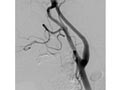

If you have serious blockage in the carotid arteries in your neck, you may need a carotid endarterectomy. During this surgery, a surgeon removes plaque buildup in the carotid arteries. The benefits and risks of this surgery must be carefully weighed, because the surgery itself may cause a stroke.

Carotid artery stenting (also called carotid angioplasty and stenting) is sometimes done as an alternative to surgery to prevent a transient ischemic attack (TIA) or stroke.

In this procedure, a doctor threads a thin tube called a catheter through an artery in the groin and up to the carotid artery in your neck. The doctor then uses a tiny balloon to enlarge the narrowed portion of the artery and places a stent to keep the artery open.

Carotid artery stenting is not as common as carotid endarterectomy, a type of surgery.